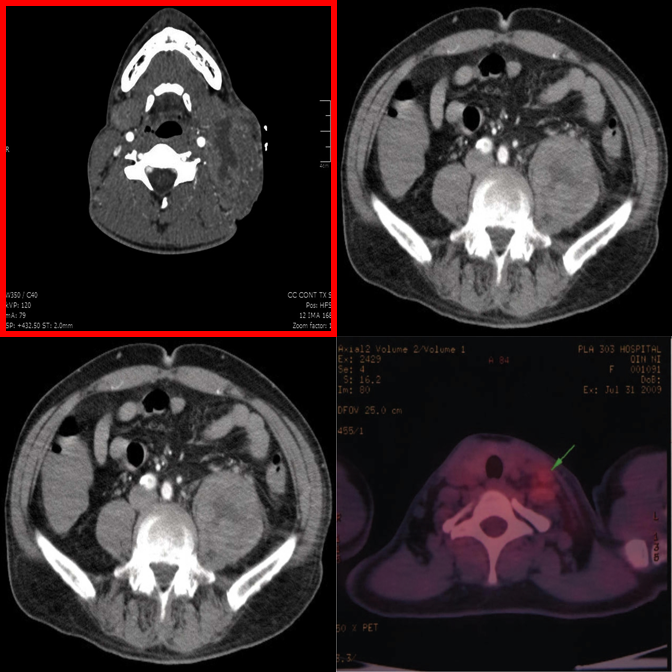

MedObvious abstracts multi-view clinical workflows into small grids where the model must identify an outlier — or correctly state that none exists.

Each tier introduces new complexity. Real examples from the benchmark are shown alongside each tier description.

Basic modality mismatches in 2×2 grids. E.g., one MRI scan among CT scans.

Broader modality pool with finer intra-class appearance variability in 2×2 grids.

Dense 3×3 grids with 8 distractors. Systematic comparison is essential.

Anatomy and viewpoint mismatches. E.g., one abdomen CT among chest X-rays.

High-saliency clinical failures: surgical hardware, fractures, gross pathology.